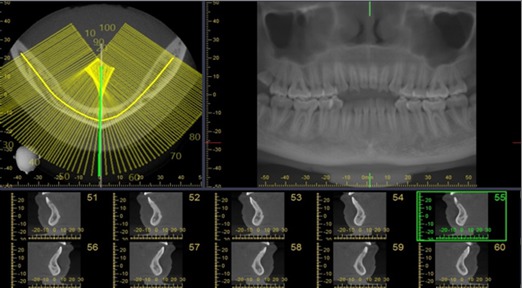

Methods: Retrospective study of 120 CBCT images in the anterior mandible were performed. All CBCT images were obtained with 3D Accuitomo (J. Morita Mfg. Corp., Kyoto, Japan) with the exposure setting of 80-90 kVp, 4-5 mA, 18 s., and FOV 10×10 cm with voxel size of 0.25 mm. The assessment of the visibility of the MIC will be recorded the detection frequencies and analyzed into the percentage. For linear measurement, the CBCT images will be analyzed from the curvedMPR. The cross-sectional images that pass through the midline, 5 mm, 10 mm, 15 mm, 20 mm from the midline (both right and left sides) will be selected and measured with the digital ruler from the viewer (i-dixel) equipped with the CBCT machine. All images will be measured in the following distances: Incisive canal to the inferior border of mandible (L1), Incisive canal to buccal plate of mandible (L2), Incisive canal to lingual plate of mandible (L3), Bucco-lingual diameter of outer contour of MIC (D1), Vertical diameter of outer contour of MIC (D2).

Results: The MIC was identified in 96% of the CBCT images. Mean (s.d.) distance from MIC to inferior border of mandible at midline, 5 mm, 10 mm, 15 mm, 20 mm from the midline were 8.74 (1.61) mm, 9.80 (1.37) mm, 10.21 (1.12) mm, 10.13 (1.89) mm, 11.03 (1.56) mm, respectively. Mean (s.d.) distance from MIC to buccal border of mandible were 4.17 (1.41) mm, 3.86 (1.28) mm, 3.74 (1.19) mm, 3.24 (1.03) mm, 3.18 (1.31) mm, respectively. Mean (s.d.) distance from MIC to lingual border of mandible were 4.02 (1.17) mm, 3.46 (1.06) mm, 3.54 (1.62) mm, 3.29 (1.47) mm, 3.84 (1.71) mm, respectively. Mean (s.d.) buccolingual diameter were 1.78 (0.37) mm, 1.97 (0.52) mm, 2.10 (0.40) mm, 2.25 (0.73) mm, 2.86 (0.51) mm, respectively. Mean (s.d.) vertical diameter were 1.84 (0.37) mm, 1.91 (0.49) mm, 2.53 (0.38) mm, 2.92 (0.46) mm, 3.11 (0.43) mm, respectively.